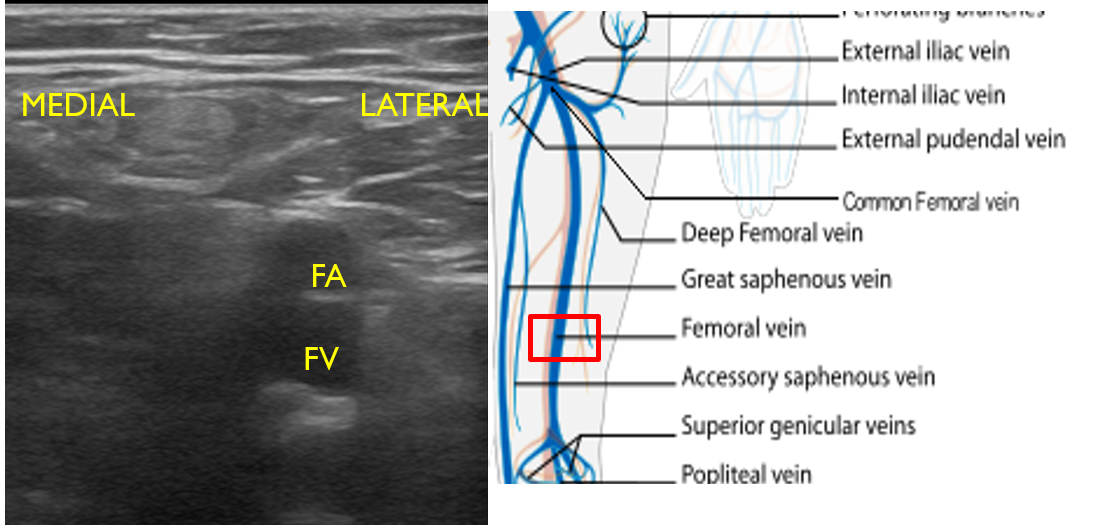

- For continual evaluation along the proximal leg, slide the transducer along the medial thigh, keeping the FA and FV in view. The FA will be superficial to the FV (Fig. 13). Compress at short intervals along the course of the vein until the pair dives deep through the adductor canal, just proximal to the knee.

- Figure 13. Femoral artery and vein seen in mid to distal upper leg with transducer orientation indicated (red rectangle).